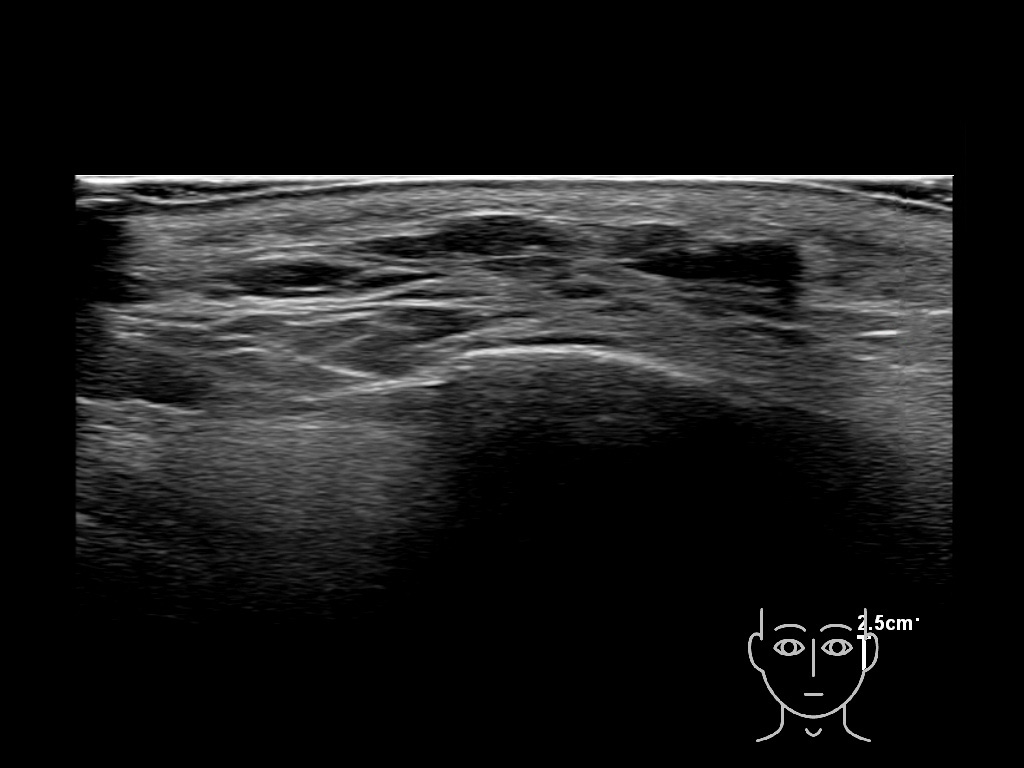

Filler behavior - Temple zygoma US

Study the first image to recognize the different layers. If you are sure about the layers, swipe to the second image to view the answer (if applicable).

Hover over an image to view the secondary image or click on the image title for more information.